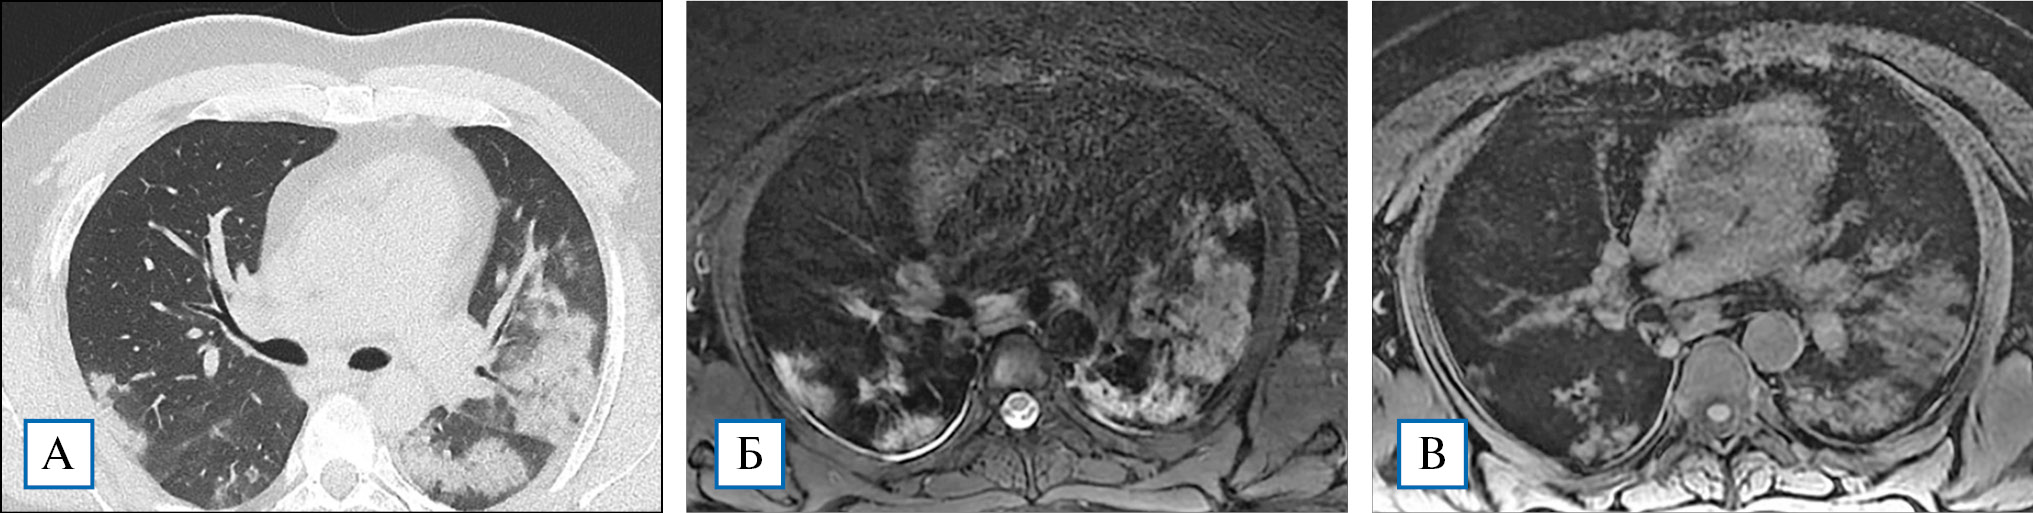

Рис. 1. Пациент, 53 года, выявляются множественные участки «матового стекла», расположенные во всех долях, преимущественно перибронховаскулярно, с нечеткими контурами — стадия КТ2 (А); аналогичные по размерам, количеству и локализации гиперинтенсивные участки визуализируются на Т٢-сканах, полученных с помощью импульсной последовательности PROPELLER FS (Б); на Т1-ВИ описанные выше изменения практически не видны (В)

Рис. 2. Пациент, 28 лет, по данным КТВР в левом легком выявляются обширные зоны консолидации сливного характера, на фоне которых видны воздушные полоски бронхов (положительная бронхограмма). Меньшие по размерам зоны уплотнения легочной ткани визуализируются в кортикальном слое правого легкого (А); на Т2-ВИ, выполненных с применением импульсного режима PROPELLER FS, зонам консолидации соответствуют гиперинтенсивные участки, полностью совпадающие по размерам и локализации с данными, полученными при КТВР (Б); на Т1-ВИ зоны поражения отображаются участками средней интенсивности сигнала, несколько меньшего размера по сравнению с КТВР и Т2-ВИ